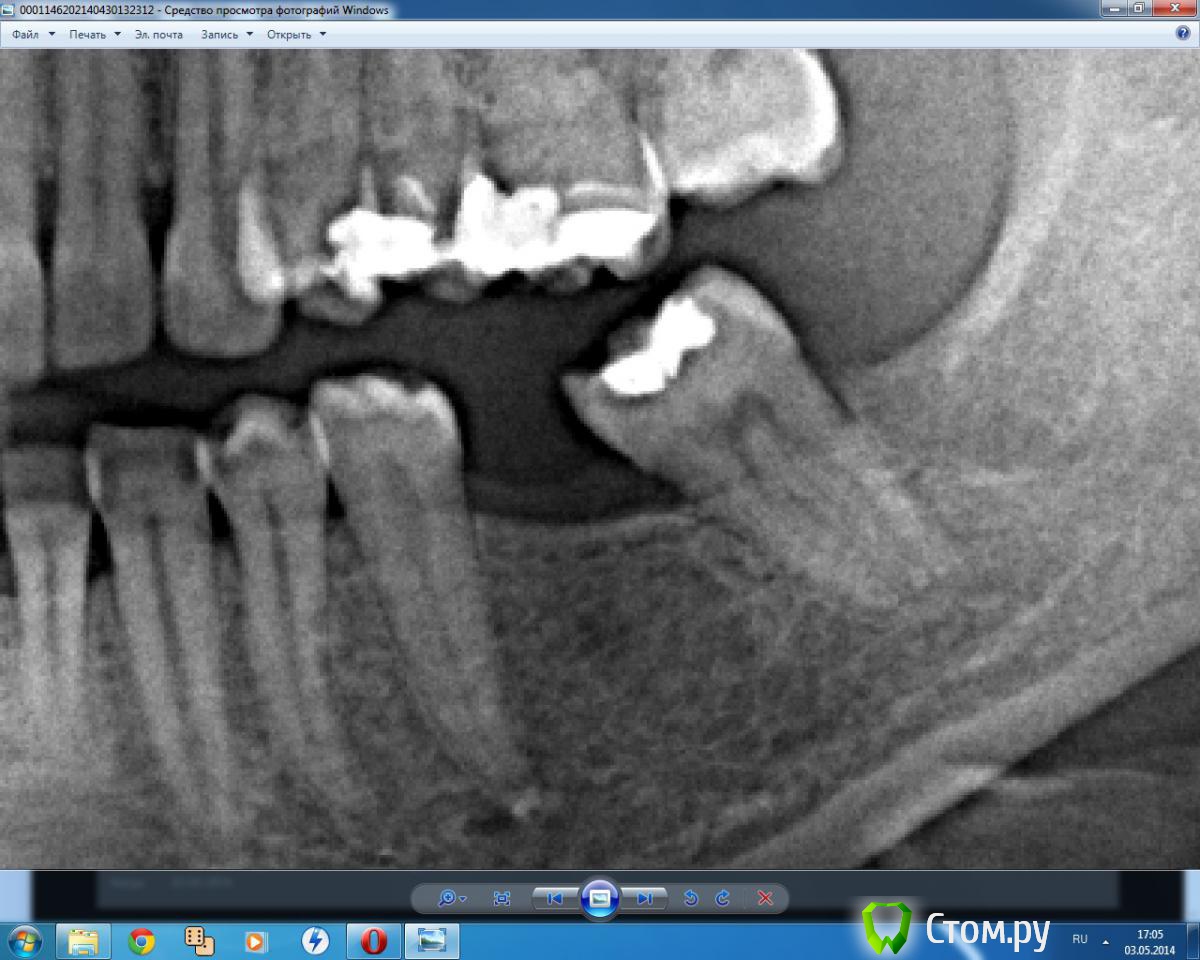

ILGAMSA Опубликовано 26 апреля, 2014 Поделиться Опубликовано 26 апреля, 2014 Может еще какие-то проблемы постановки в данной области?Проблемы могут быть в том, что имплант будет ставить некуда.Иногда лучше поступить так: http://s57.radikal.ru/i156/1404/be/4af4533b44be.jpg 7 Ссылка на комментарий

Ayrat_zub Опубликовано 5 мая, 2014 Поделиться Опубликовано 5 мая, 2014 Меня ортодонт часто просит установит винт там где места оч-очень мало, на снимках менее 2мм. между корнями. Развожу руками. Прошу найти др.место, нет и все тут и только тут, вот сегодня опять спорили. Проблемы могут быть в том, что имплант будет ставить некуда.Иногда лучше поступить так: http://s57.radikal.ru/i156/1404/be/4af4533b44be.jpgвот такой вариант покажите) я взял на вооружение)) всем хирургам показал) Ссылка на комментарий

zzkz Опубликовано 6 мая, 2014 Поделиться Опубликовано 6 мая, 2014 вот такой вариант покажите) я взял на вооружение)) всем хирургам показал)что это и как его едят?И если тяга нужна не за молярами а с вестибулярки, например между 5 и 6 зубами? Ссылка на комментарий

АнтонТЛТ Опубликовано 6 мая, 2014 Поделиться Опубликовано 6 мая, 2014 что это и как его едят?И если тяга нужна не за молярами а с вестибулярки, например между 5 и 6 зубами?Мини- или микропластина для остносинтеза.Если тяга нужна между 5 и 6 зубами, то пластину можно прикрутить просто вестибулярно Ссылка на комментарий